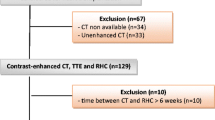

A total of 1864 patients were referred to the pulmonary hypertension centre during the period studied and underwent right heart catheterisation: of these 145 had a documented diagnosis of COPD from a respiratory specialist. One hundred and two had MRI and RHC within 90 days so were included in the study. There were 87 patients with pulmonary hypertension (69 of these had severe pulmonary hypertension) and 15 patients without pulmonary hypertension (please see Fig. 1 for the patient diagnostic pathway). Figure 2 shows the flow of patients within the diagnostic pathway. There were 24 with GOLD severity 1, 40 with GOLD severity 2, 18 with GOLD severity 3 and seven with GOLD severity 4; 13 patients did not have spirometry results available for analysis. Of the 102 cases of COPD included in the study, 75 had spirometric evidence of airflow limitation (FEV1/FVC ratio <0.7), and the remaining 17 had evidence of emphysema on CT. Table 1 shows the patient demographics and clinical characteristics for the whole group and split into no PH (mPAP <25 mmHg), PH (mPAP 25 to ≤35 mmHg) and severe PH (mPAP ≥35 mmHg).